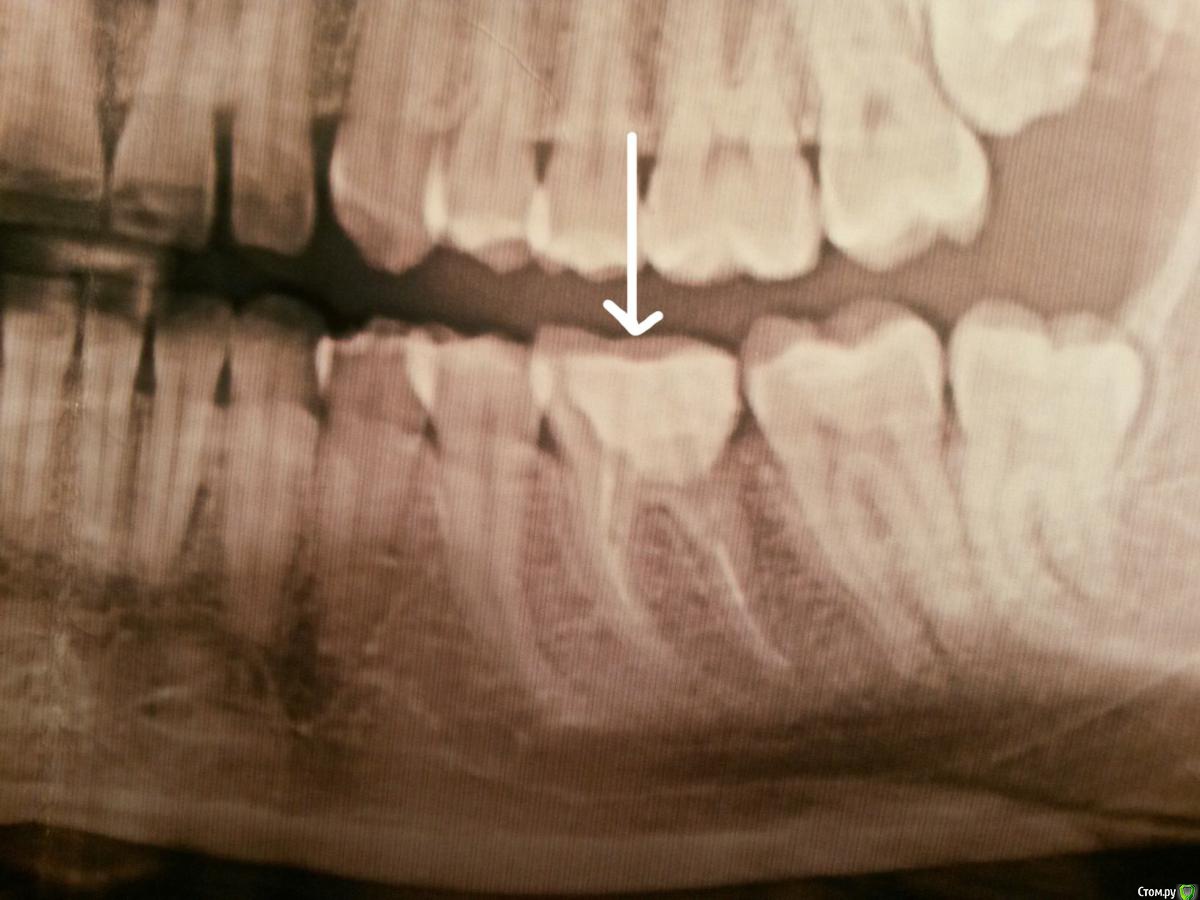

Melancholia Опубликовано 13 февраля, 2018 Поделиться Опубликовано 13 февраля, 2018 Депульпировали зуб месяц назад, нижняя 6 ка. Под временной пломбой откололась стенка зуба ниже уровня десны и началось воспаление десны, там где была эта стенка. Поставили постоянную пломбу которая очень большая(от моего зуба остался корень и одна стеночка), воспаление усилилось, температура 37,2, красная десна, кровоточивость,карман между десной и зубом, если надавить чуточка гноя, странные зудящие ощущения в десне, при ходьбе как будто пульс в этой десне. Пошла к другому врачу, сказали пломба нависающая, контактный пункт плохой и пломба недостаточно широкая из-за этого карман и все пр.Переделали большую часть пломбы. Было это две недели назад. Но воспаление не ушло. Карман ушел, сильная опухлость и покраснение десны ушли, но вечерами температура 37,2 , сбоку по краю зуба из десны торчит что-то красное, ощущения неприятные, но несильные, если нажать чуть-чуть, то десна в этом месте, где красное чуть чуть отходит и оттуда кровит немножко, откуда то будто изнутри, ощущения зуда вокруг зуба несильные. Гноя вроде нет, контактные пункты хорошие, нить проходит как надо. Полоскаю хлоргексидином, фурацилином, мажу Холисалом, временами ощущения легче, но до конца не проходит. Неделю назад показала своему стоматологу он сказал что стало лучше и что десна со временем пройдет. Никогда не было проблем с деснами, и нигде кроме этого места проблем нет. Сколько ждать? Почти месяц десна воспалена. Прилагаю рентген, до того как переделали нависающую пломбу, чтоб показать каналы, мало ли что.. нового снимка еще не делала, т.к. сказали что каналы норм и дело не в них. Зуб не болит, но поутру ощущение что он мешается, будто за ночь стал выше. Ссылка на комментарий